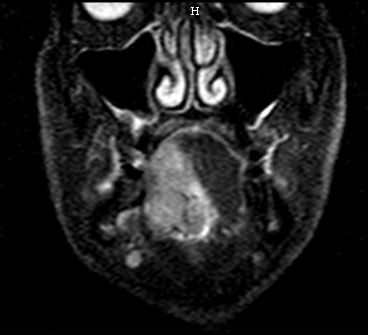

Klinik Großes Zungenrand-Karzinom mit überschreiten der Mittellinie, Befall der Tonsille rechts.

Diagnostik Zunächst CUP mit Lymphknotenpaket links Level III. Im MRT Zungengrundtumor nahe der Mittellinie.